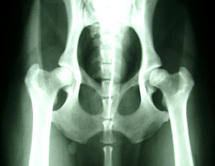

PARIS, 6 juillet 2011 (AFP) - L'augmentation des doses de radioactivité délivrées aux patients par imagerie médicale, en particulier par les scanners, est devenue préoccupante et doit être maîtrisée, a alerté mercredi l'Autorité de sûreté nucléaire (ASN).

"Les scanners représentent 10% des examens et 58% des doses reçues", a relevé M. André-Claude Lacoste, président de l'ASN, en soulignant la "position écrasante" de ces appareils dont les performances ne sont pas toujours utilisées à bon escient.

En 5 ans, on a enregistré une augmentation de 47% des doses délivrées aux patients (1/4 de la population française par an) a montré le rapport IRSN/InVS de 2010, rappelle l'ASN.

Selon l'ASN, qui réitère son "message d'alerte" sur ce "souci majeur", le remplacement de certains examens de scanner par l'imagerie par résonance magnétique (IRM) s'impose.

La France ne possède que 8,7 IRM par million d'habitants contre une moyenne européenne de 20.

Ce manque d'IRM en France participe au "surcroît non justifié" d'irradiation médicale en plus de "mauvaise pratique médicale", pointe l'ASN qui milite pour un "rééquilibrage du parc français entre scanners et IRM".

L'IRM, qui n'émet pas d'irradiation, a des applications privilégiées: le cerveau --en particulier en urgence pour les attaques cérébrales (AVC)--, la moelle épinière, la rhumatologie et les enfants.